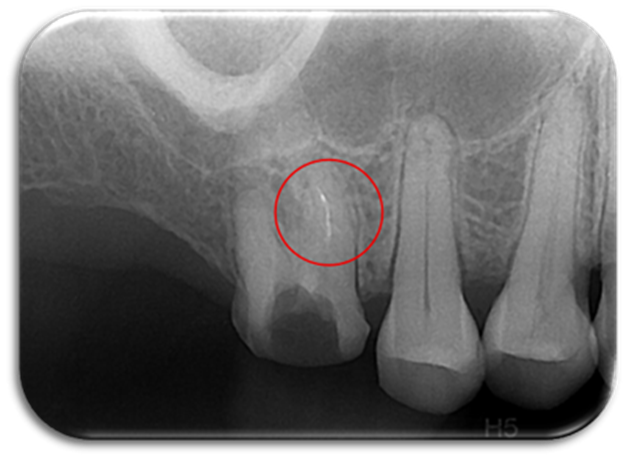

▲图源:搜狐千里眼

在根管治疗时,医生使用根管锉(钻)将牙齿根管内部的病损组织以及感染物质清除,这个过程叫做“根管预备”。此过程中,如果根管锉(钻)在根管内折断,专业术语叫做“器械分离”,这就是俗称的“断针”。

▲从根管内取出“断针”

▲我院为多位转诊患者成功取出“断针”